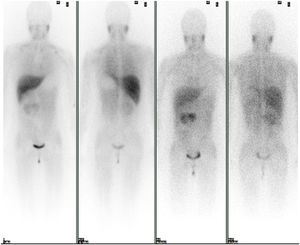

Se solicitó un estudio de localización mediante resonancia magnética nuclear (RMN) abdominal (figura 1 del anexo), que mostró una gran masa abdominal a nivel paraaórtico derecho compatible con un paraganglioma intraabdominal y estudio de extensión mediante tomografía computarizada (TC) toracoabdominal con contraste (figura 2 anexo) y gammagrafía con MIBG 131 (figura 3 anexo), que no mostraron lesiones a ningún otro nivel.

Estudio gammagráfico con MIB 131. Estudio de extensión con MIBG 131. Se observa captación fisiológica en hígado y salivares y eliminación urinaria. En el área cardiaca existe una actividad muy tenue e irregular, en probable relación con el exceso de catecolaminas. Se objetiva presencia de receptores adrenérgicos en la masa abdominal conocida.